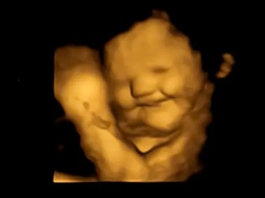

Thai nhi cười khi mẹ ăn cà rốt

Chi NuocAnh - 23/09/2022 0